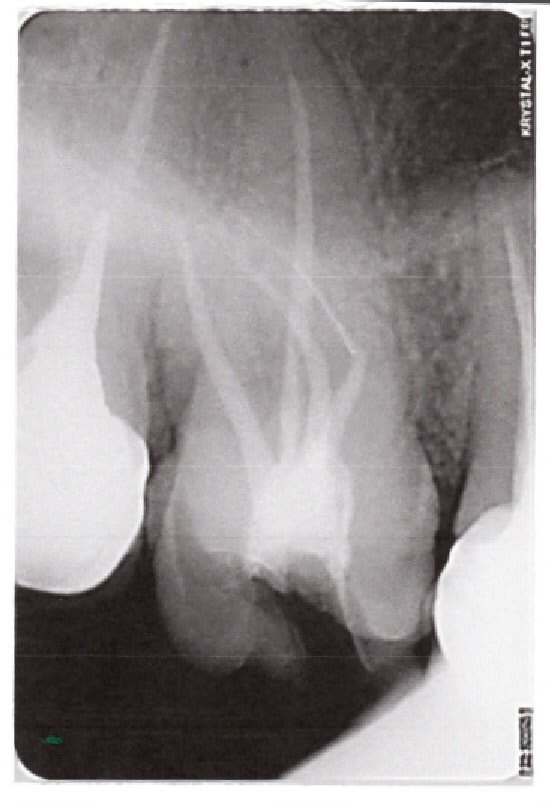

Pas sur de moi, lachmar, mais tu as peut etre un hiatus entre l'axe de ton bout d'instrument et l'axe de départ. Peut etre que le bon trajet est matérialisé par le tracé vert. J'ai agrandi un peu.

Fauxcanalavoir djnawh - Eugenol

Fauxcanalavoir0 yszo1r - Eugenol